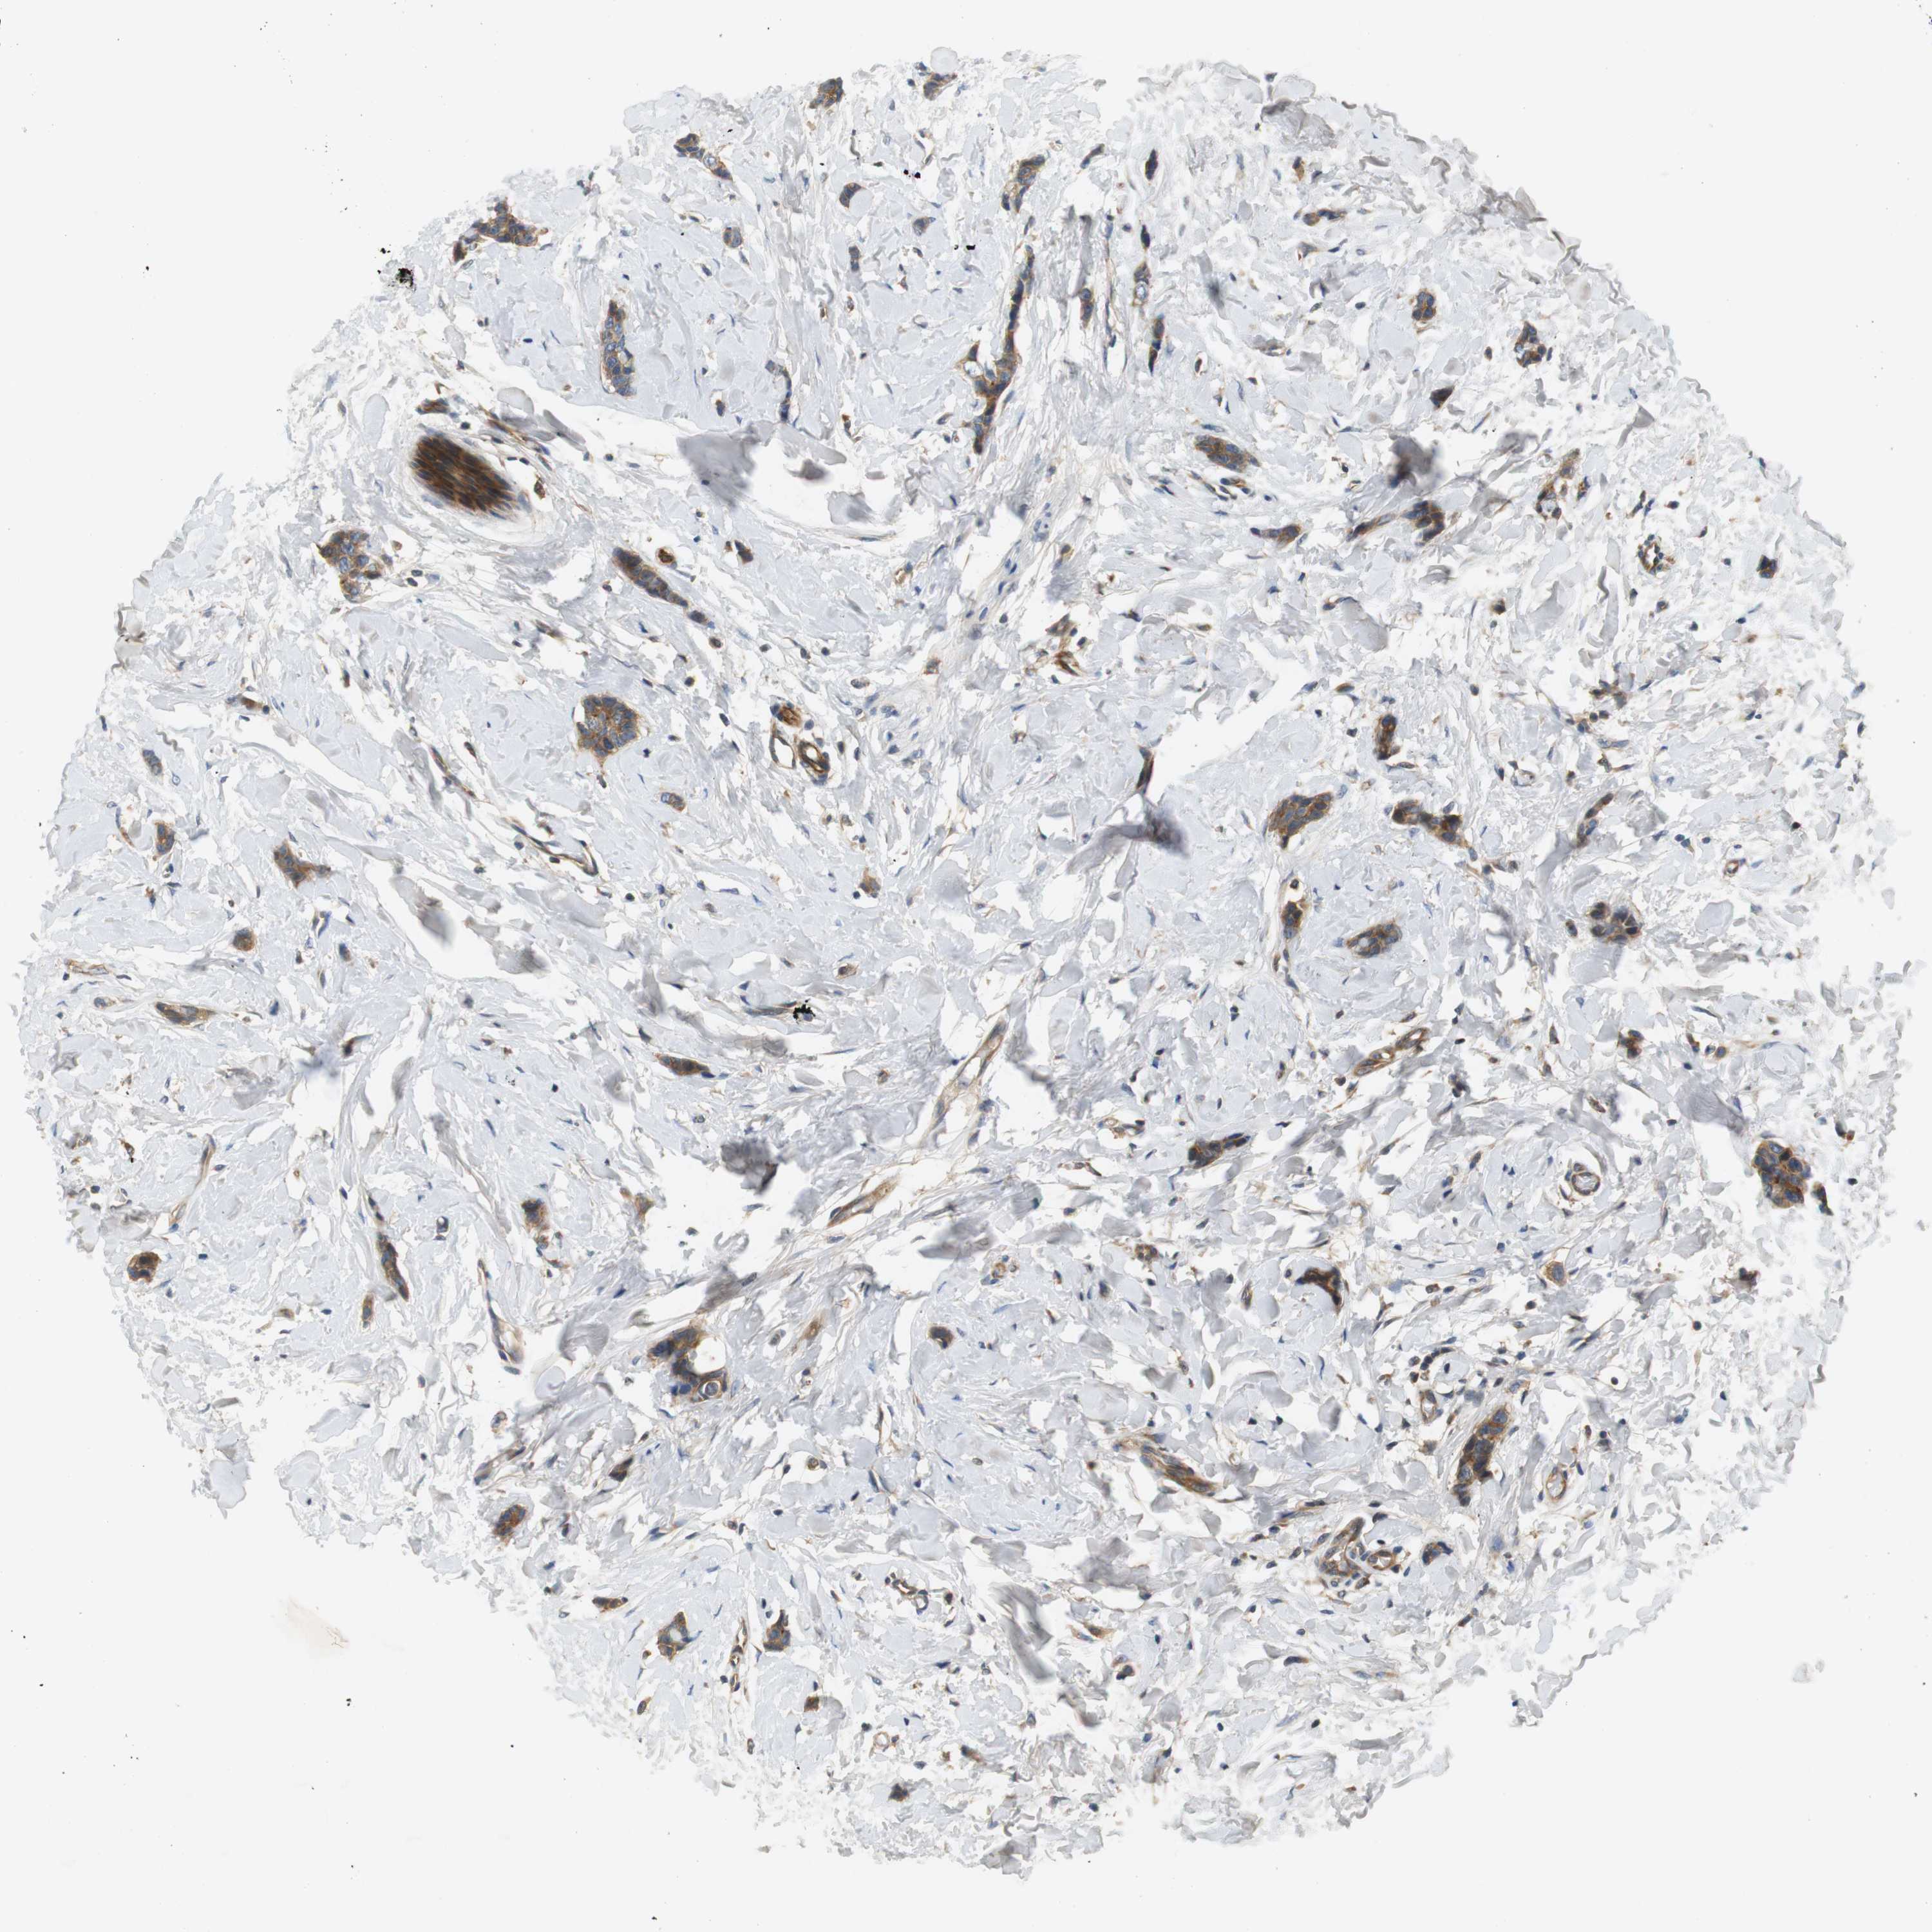

CANCER BREAST CANCER Show tissue menu

BRCA TCGA BRCA VALIDATION PROTEIN EXPRESSION

ANTIBODIES

AND

VALIDATION